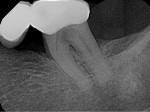

The patient had maintained his oral health for several years until furcal decay was noted on tooth No. 18 at his recall examination (Figure 2), and upon the removal of the original fixed partial prosthesis the extent of the decay was fully appreciated (Figure 3). The patient had failure of implants at sites Nos. 19 and 20. Given his medical history as well as his history of failed dental implants, the patient was reluctant to attempt any type of implant surgical intervention and wanted to explore possible treatment alternatives. Thus, it was decided to restore the mandibular left side with a fixed partial prosthesis with abutment teeth at Nos. 18 and 20.

Decay was initially removed and root canal therapy (RCT) was completed on tooth No. 18. As was evident in the radiograph (Figure 4) tooth No. 18 presented with C-shaped mesial and distal roots, which appeared as two single canals. Using advanced microscopy aided by an apex locator, the apex of the distal root had clinically terminated 2 mm to 3 mm shorter than the radiographic apex. After completion of RCT using the WaveOne Gold system (Dentsply Sirona, dentsplysirona.com), a core buildup was placed using a combination of flowable and packable composite. The No. 18 hemisection was then accomplished, and each individual retained root was prepared as if it were a premolar tooth, in the expectation of acting like a single-unit abutment crown. Crown lengthening was then performed in the interseptal bone between the retained roots of tooth No. 18. A full-thickness flap was elevated and the soft tissue debrided between the roots, and an end-cutting bur was used to carefully remove 2 mm to 3 mm of interseptal bone (Figure 5).